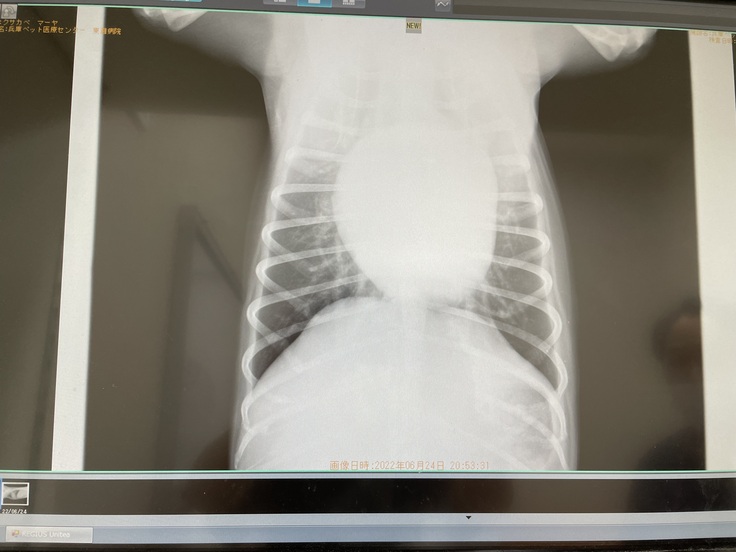

【現在のマーヤの心臓エコー写真】心臓肥大により心臓が気管を押し上げて気道が狭くなっています。

【パンパンに肥大したマーヤの心臓】